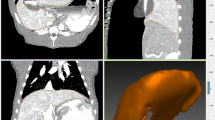

Three-dimensional modeling and point mapping

The segmented hepatic veins were converted to 3D polygonal models of the hepatic vein tree using the MITK software. Bifurcation points were used for point mapping, rather than center of vessel lumens because of the potential for achieving a greater consistency with the tools used. The first step was to determine the common bifurcation points within each pig separately, which adequately represented the central to peripheral range of the models. Points were mapped using the transverse, sagittal, and coronal views and were confirmed on the 3D models (Fig. 1). The amount of bifurcation points varied between pigs (7–16 points). Rare trifurcations were treated as bifurcations between the two largest of the three branches. The consistency of the points was then re-examined by an experienced radiologist. The use of branching points allowed reliable measurement of liver motion in different locations [42] (Fig. 2).